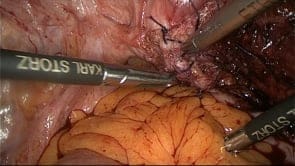

Vascular Complication during Laparoscopic Pelvic Surgery-Injury to inferior epigastric artery. (Video)